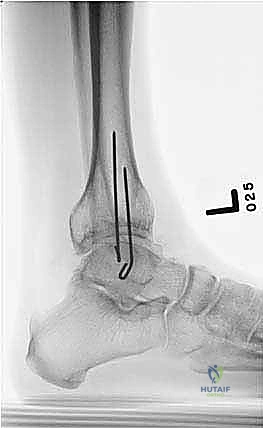

المرحلة الثالثة: قطع عظمة الشظية (Fibular Osteotomy)

للسماح للظنبوب (العظمة الرئيسية) بالتحرك والتصحيح، يجب أولاً قطع عظمة الشظية. يتم ذلك عبر شق جراحي صغير جداً (حوالي 1-2 سم) في الثلث السفلي أو الأوسط من الساق.

المرحلة الرابعة: قطع العظم عبر الجلد (Percutaneous Tibial Osteotomy)

هنا تتجلى مهارة الجراحة بأقل تدخل:

1. يُجري الدكتور هطيف